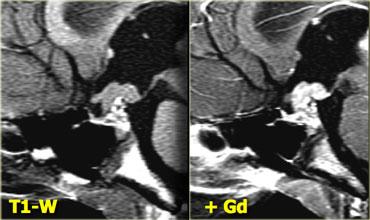

U Tuyến Yên Vi Thể

Theo định nghĩa, u tuyến yên vi thể có đường kính nhỏ hơn 10 mm và nằm trong tuyến yên.

Các hình ảnh này minh họa một trường hợp điển hình: trên chuỗi xung T1W, tổn thương có đường kính khoảng 3-4 mm, giảm tín hiệu nhẹ so với mô tuyến yên bình thường, nằm trong tuyến yên.

Trên chuỗi xung T2W, tổn thương tăng tín hiệu nhẹ.

Chẩn đoán phân biệt: u tuyến yên vi thể hoặc nang khe Rathke (hai thực thể này có thể không phân biệt được với nhau).

Độ nhạy của MRI không tiêm thuốc tương phản từ trong phát hiện u tuyến yên vi thể vào khoảng 70%.

Không phải lúc nào cũng cần tiêm thuốc tương phản từ đường tĩnh mạch để phát hiện u tuyến yên vi thể, vì những bệnh nhân có kết quả chụp âm tính thường nhận được phác đồ điều trị triệu chứng tương tự như bệnh nhân có u vi thể (thông thường đây là những phụ nữ có triệu chứng tăng prolactin máu).

Mục đích của việc chụp MRI là để loại trừ các tổn thương kích thước lớn.

Đối với các ứng viên có thể phẫu thuật (ví dụ: bệnh nhân thất bại với điều trị nội khoa hoặc bệnh lý tuyến yên không đáp ứng với điều trị nội khoa như bệnh Cushing), cần thiết phải tiêm thuốc tương phản từ để xác định vị trí tổn thương một cách chính xác nhất có thể.

Trên phim chụp không tiêm thuốc tương phản từ, có thể phát hiện khoảng 70% tổng số u tuyến yên vi thể.

Khi tiêm gadolinium, tỷ lệ âm tính giả có thể giảm từ 30% xuống còn 15%.

Như đã đề cập trước đó, điều này thường không ảnh hưởng đến quyết định xử trí lâm sàng của bệnh nhân.

Hình ảnh chuỗi xung T1W và T2W mặt phẳng coronal, cùng với hình ảnh chuỗi xung T1W trước và sau tiêm gadolinium.

Ở bệnh nhân này, tổn thương trong tuyến yên chỉ có thể phát hiện được sau khi tiêm thuốc tương phản từ đường tĩnh mạch.

Chẩn đoán phân biệt: u tuyến yên vi thể hoặc nang khe Rathke.